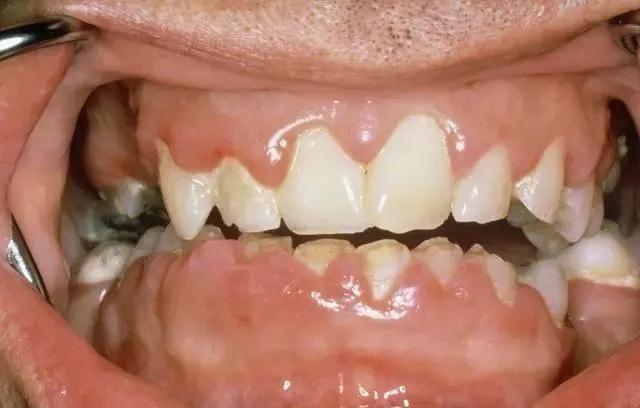

3、牙周变形

牙周变形一般在青年人中出现,牙周变形是因为牙周组织发生退行性改变引起的,出现了牙周纤维破坏或牙槽骨吸收的情况,从而出现牙齿松动以及移动的情况。